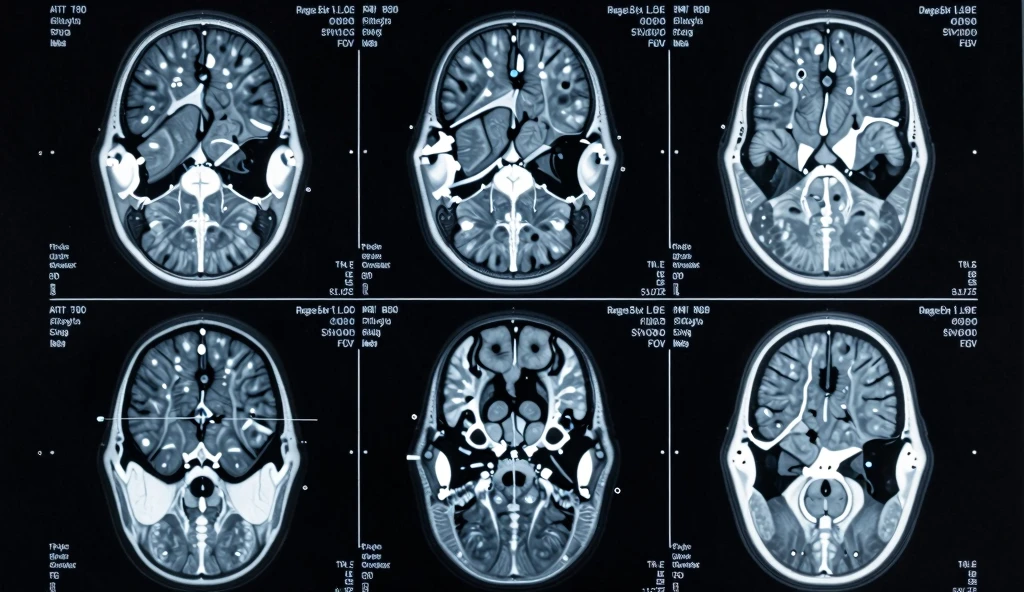

T2 hyperintensity symptoms explained: early signs, causes, risks, and treatment options. Understand your MRI results with this complete guide.

If you’ve recently had an MRI scan, you may have come across the term T2 hyperintensity symptoms in your medical report. For many people, this phrase can sound confusing or even alarming. What exactly does it mean? Should you be worried? And most importantly—what symptoms are linked to it?

In simple terms, T2 hyperintensity-symptoms refer to the clinical signs associated with bright spots seen on a specific type of MRI scan called a T2-weighted image. These bright areas can indicate various underlying conditions, ranging from mild and harmless to more serious neurological disorders.

A T2-weighted MRI is a type of imaging that highlights fluid and inflammation in the body. When something appears “hyperintense,” it means it shows up brighter than surrounding tissue on the scan.

These bright areas can appear in different parts of the body, but they are most commonly found in the brain and spinal cord.